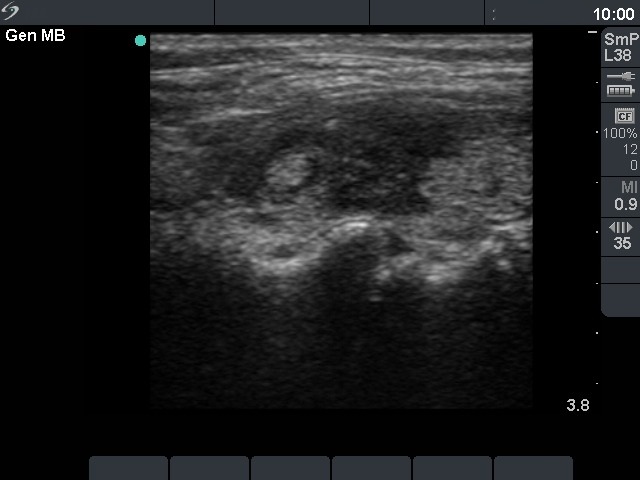

Ultrasonography. The thyroid was echonormal and presented several hypoechoic areas. The pattern in the right lobe was obviously focal form of lymphocytic thyroiditis.

A relatively large hypoechoic areas was found in the left lobe. The lesion had irregular borders. At first sight, this presentation of the left lobe could be interpreted as the central hypoechoic area-type form of lymphocytic thyroiditis. However, the hypoechoic lesion was not entirely surrounded with echonormal thyroid tissue. More importantly, the central hypoechoic areas-type form is almost always bilateral.

The sonographic pattern is remarkable. On the one hand, the tumor was identical to other more active foci of Hashimoto's thyroiditis. The only difference was the size of this lesion which was larger than other lesions observed in the thyroid. In the case of Hashimoto's thyroiditis neither the irregularity of border, nor the increased vascularization has any relevance. On the other hand, the tumor had microcalcifications and was significantly larger than other foci. The lesson to draw is the comparison of various lesions: if we detect a lesion which differs from others regarding the echogenicity, the size or the vascularization, it is advisable to perform FNA.

The distinction of central hypoechoic area-type form of LT from a large hypoechoic nodule is in part based on noticing whether the pattern is bilateral or unilateral. While the former is almost pathognomonic of LT, the latter excludes this special form of LT and significantly increases the probability of a true nodule.